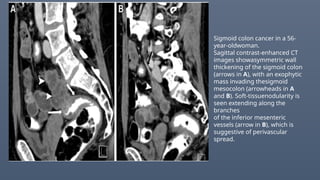

Sigmoid colon cancer in a 56-

year-oldwoman.

Sagittal contrast-enhanced CT

images showasymmetric wall

thickening of the sigmoid colon

(arrows in A), with an exophytic

mass invading thesigmoid

mesocolon (arrowheads in A

and B). Soft-tissuenodularity is

seen extending along the

branches

of the inferior mesenteric

vessels (arrow in B), which is

suggestive of perivascular

spread.

Sigmoid colon cancerin a 56- year-oldwoman. Sagittal contrast-enhanced CT images showasymmetric wall thickening of the sigmoid colon (arrows in A), with an exophytic mass invading thesigmoid mesocolon (arrowheads in A and B). Soft-tissuenodularity is seen extending along the branches of the inferior mesenteric vessels (arrow in B), which is suggestive of perivascular spread.